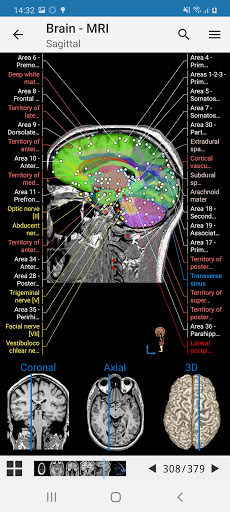

IMAIOS e-Anatomy adalah atlas anatomi manusia untuk dokter, ahli radiologi, mahasiswa kedokteran, dan teknisi radiologi. Dapatkan cuplikan lebih dari 26.000 gambar medis dan anatomi secara gratis sebelum berlangganan atlas anatomi manusia terperinci kami.

e-Anatomy memiliki lebih dari 26.000 gambar yang berisi serangkaian gambar dalam tampilan aksial, koronal, dan sagital serta radiografi, angiografi, gambar diseksi, bagan anatomi, dan ilustrasi. Semua gambar medis diberi label dengan cermat, lebih dari 967.000 label tersedia dalam 12 bahasa termasuk Terminologia Anatomica Latin.

- Gulir set gambar dengan menyeret jari Anda

- Perbesar dan perkecil

- Ketuk label untuk menampilkan struktur anatomi